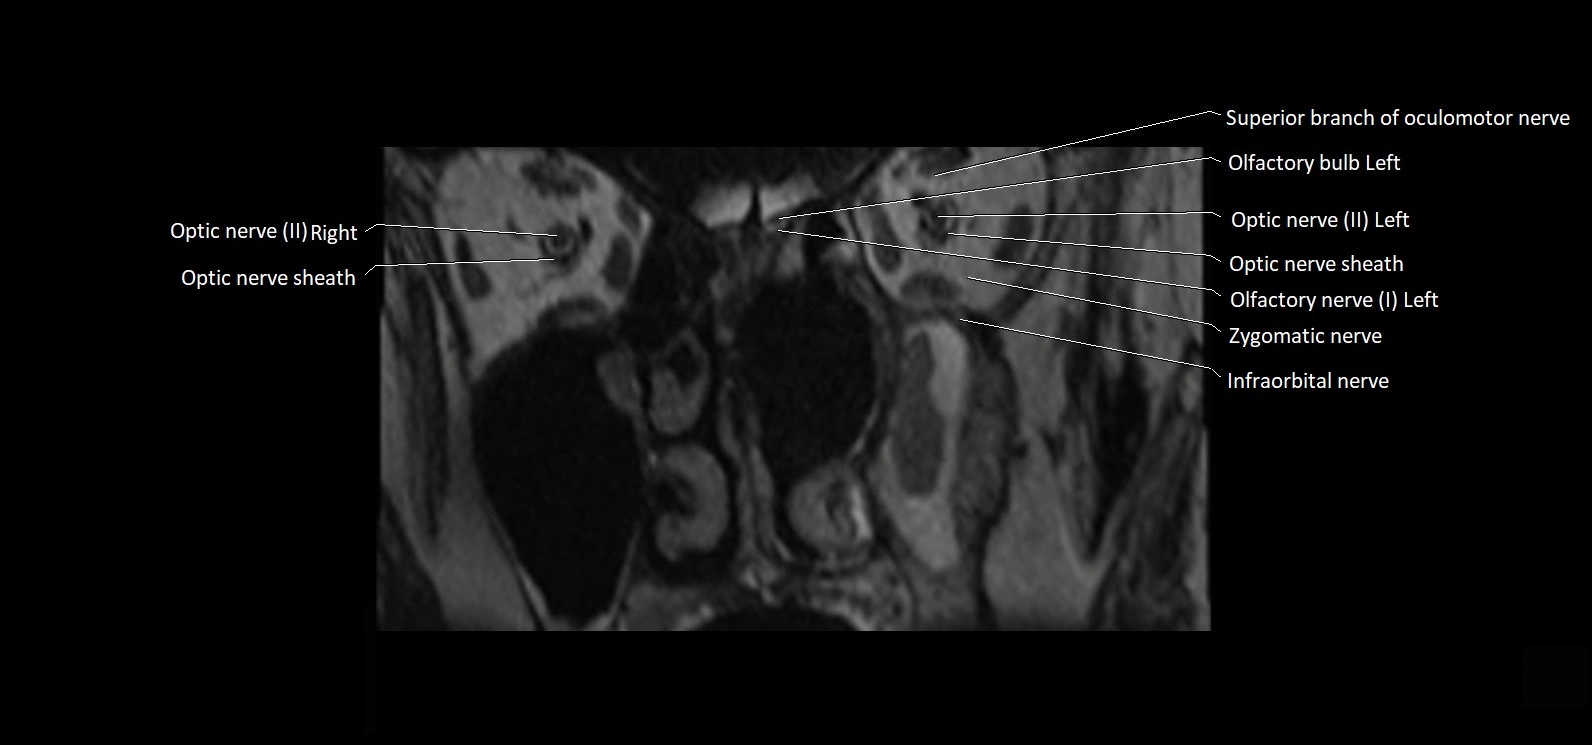

MRI Appearance

• The abducens nerve is a small, thin, linear structure

• Best visualized on high-resolution T2-weighted 3D MRI sequences (e.g., FIESTA or CISS)

• Seen as a hypointense (dark) line running from the brainstem at the pontomedullary junction, traversing the prepontine cistern, and entering Dorello’s canal under the petrosphenoidal ligament, then into the cavernous sinus, and finally the orbit

• May be challenging to visualize in standard MRI due to its small size

• Pathology may be inferred by absence, displacement, or enhancement of the nerve